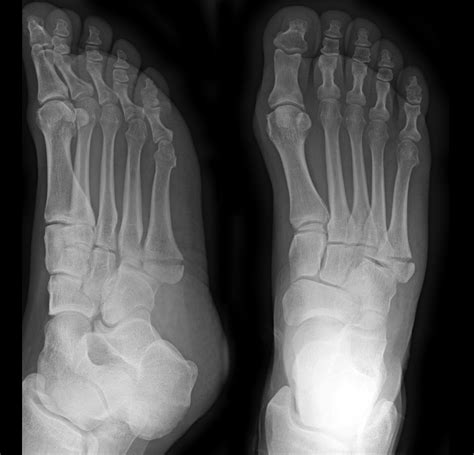

Avulsion fracture of the 5th metatarsal from www.sportsorthopaedicspecialist.co.uk You have sustained a fracture to the base of the 5th metatarsal of your foot, which is known as an avulsion fracture. Fractures are common in the fifth metatarsal and normally occur with sporting activities. Literature favours operative treatment but in practice non operative treatment gives similiar results.if not disl. 5th metatarsal fractures have been quite common among elite soccer players in the english premier league over the past five years. Usually there is no need for surgery; Avulsion fractures of the fifth metatarsal base: Patients with this condition typically experience a sudden onset of sharp, intense outer foot or ankle. Medical treatment for 5th metatarsal avulsion fracture.

Very rarely is it necessary to operate on these fractures acutely. Avulsion fractures of the tuberosity are the most common fractures involving the proximal fifth metatarsal. 5th metatarsal fractures can vary in location, severity and type including avulsion fracture, stress fracture, jones' fracture, displaced fracture signs and symptoms of a 5th metatarsal fracture. Traditionally this avulsion fracture has been ascribed to the insertion of peroneus brevis and is caused by forcible inversion of the foot in plantar flexion radiographic features. I rolled my ankle on 5 october and broke 4th and 5th. Os peroneum is an accessory bone (ossicle) located at the lateral side of the tarsal cuboid, proximal to the base of 5th metatarsal, commonly mistaken for a fracture. When there is significant displacement a in rare situations it may be necessary to undertake reconstructive surgery which would repair not only the fracture (often with bone grafting). Fifth metatarsal fracture, proximal fifth metatarsal fracture, jones fracture, fifth metatarsal base fracture. I am 6 weeks post surgery on my 5th displaced metatarsal fracture. 5th metatarsal fractures have been quite common among elite soccer players in the english premier league over the past five years. Jones fracture is a difficult fracture to heal due to limited blood supply to that area and often surgery. This one is tricky.due to the specific vascularity in that region it is of uttmost importance to properly select surgical candidates. Fractures of the proximal fifth metatarsal pose an important diagnostic challenge.

The 5th metatarsal is the outer bone that connects to your little an avulsion fracture occurs when a tendon pulls a piece of bone away from the rest of the bone. Fifth metatarsal fractures are notoriously slow healing fractures, but after ten weeks, especially since you had surgery, under most circumstances you. Most common fracture at base of 5th metatarsal. Based on landmarks along joint between 4th and 5th metatarsals proximally. Avulsion fractures of the fifth metatarsal base:

You have sustained a fracture to the base of the 5th metatarsal of your foot, which is known as an avulsion fracture. This part of the bone is attached to tendon. 5th metatarsal fractures have been quite common among elite soccer players in the english premier league over the past five years. Early functional treatment of a 5th metatarsal fracture using an orthopedic boot. This can occur at the ligament by the application of forces external to the body (such as a fall or pull). Swiss surgery = schweizer chirurgie = chirurgie suisse = chirurgia svizzera. If not displaced or comminuted, these fractures uniformly heal well with. Metatarsal fracture avulsion fracture stress fracture jones fracture bow legged sprained ankle foot pain videos funny surgery. Most common fracture at base of 5th metatarsal. 5th metatarsal fractures account for almost one quarter of all metatarsal injuries, and most occur at the base of the bone. Distal radius fractures programme online course: Posted 7 years ago, 149 users are following. Patients with this condition typically experience a sudden onset of sharp, intense outer foot or ankle.